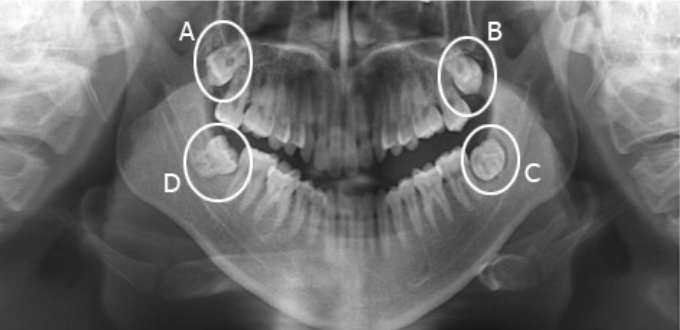

At Dentel Dentistry, each customer will have an X-ray with CT Cone Beam machine during the general visit. X-rays and 3D films will allow the doctor to clearly see the shape and pattern of wisdom teeth. From there, giving a suitable and safe extraction plan.

Teeth 8 are teeth with complex eruption patterns. Especially the root part. In order to be able to accurately diagnose as well as plan appropriate extraction, customers will conduct imaging X-ray, 3D films with high-tech equipment. Thanks to that, the complete shape of the 8 tooth can be clearly seen, even in the case of an implantation of the gums, providing an accurate - perfect treatment regimen.

With the X-ray film, the film is scanned from the CT Cone Beam machine, allowing clear identification to the millimeter. Helping the doctor can absolutely avoid the limit of non-invasive as well as not cause damage to soft tissue and adjacent teeth. Thanks to that, you can be assured of choosing Dentel Dentistry to perform the removal of wisdom teeth quickly - safely and effectively.

Film taken before wisdom tooth extraction